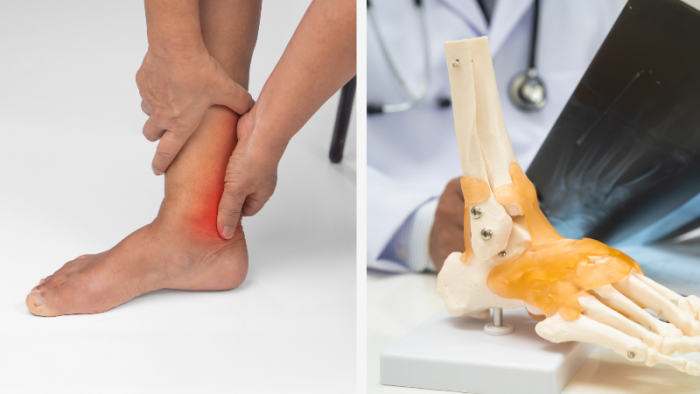

L’arthrose est une maladie chronique des articulations. Elle correspond à une dégradation du cartilage, le tissu qui permet aux os de glisser sans frottement. Avec le temps, toute l’articulation peut être touchée, y compris l’os situé dessous. Elle provoque surtout des douleurs mécaniques, une raideur, une gêne dans les mouvements et parfois une diminution de la mobilité. Elle touche souvent le genou, le gros orteil (hallux rigidus), la cheville, la hanche, les doigts ou la colonne vertébrale.

Les diagnostics de l’arthrose reposent d’abord sur l’interrogatoire et l’examen clinique : douleur mécanique arthrosique, raideur brève, gêne fonctionnelle, parfois craquements ou déformation. La radiographie confirme souvent ces diagnostics en montrant un pincement articulaire, des ostéophytes ou une atteinte osseuse. L’IRM est rarement nécessaire, sauf cas complexes. Des analyses sanguines ou une ponction articulaire peuvent être utiles surtout pour écarter d’autres causes, comme une arthrite inflammatoire ou infectieuse.

Les complications des arthrodèses près de Salon de Provence

Les complications possibles incluent l'infection, une inflammation, des saignements, des douleurs persistante, une raideur, un retard de consolidation ou pseudarthrose, déplacement ou rupture du matériel, irritation nerveuse, phlébite. Et parfois atteinte des articulations voisines à long terme.

Selon la zone opérée (pied, cheville, orteil...), il peut aussi exister un risque de lésion vasculaire, de plaie durale ou de complications inflammatoires liées à la greffe osseuse. Une surveillance postopératoire régulière est essentielle pour dépister rapidement ces problèmes et adapter le traitement avec le chirurgien et l’équipe de rééducation spécialisée.